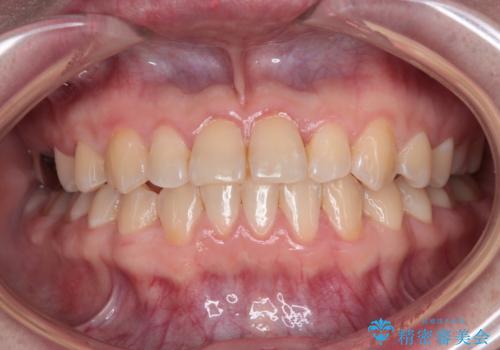

- 前歯の反対咬合を気にして来院された患者様です。

当院にて同様の咬み合わせを治療した方からのご紹介ということもあり、ご紹介者と同じワイヤー矯正で早めに治療を終えることを希望されました。

骨格的に下顎が前方に位置していましたが、歯列矯正で改善できると判断し、ワイヤー装置にて矯正治療を行うこととしました。

このような咬み合わせの方の多くは、舌の突出癖が強い傾向にあり、反対咬合改善後に開咬となってしまい、なかなか治療が終わらないことがあります。

こちらの患者様は、舌のトレーニングを治療開始前から徹底的に実践していただき、僅か8ヶ月という短期間で治療を終えることができました。